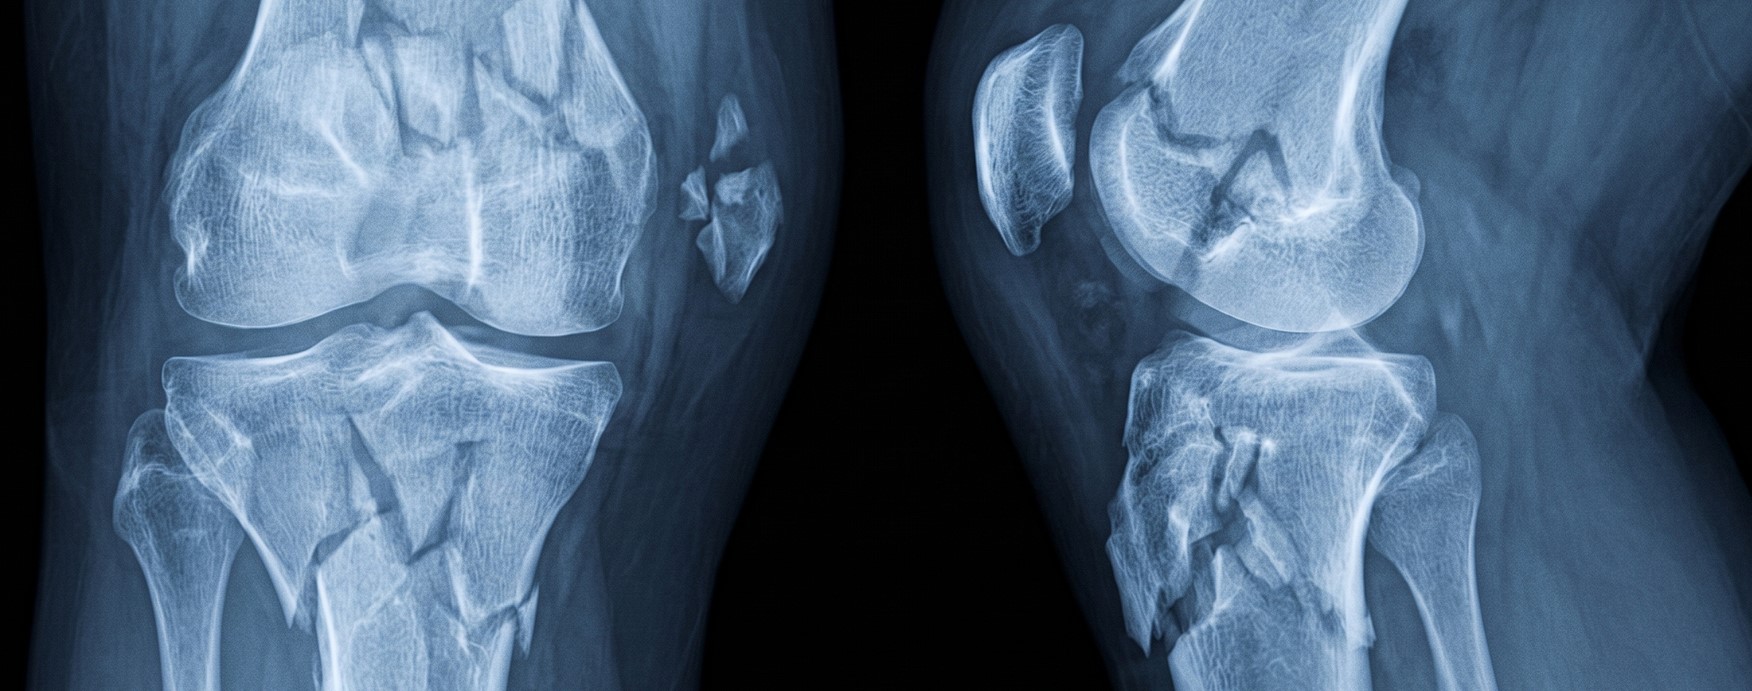

В настоящее время проблема реабилитации после травм стоит особенно остро в связи с увеличением количества людей, ежедневная профессиональная деятельность которых связана с риском для жизни.

В рамках государственных программ реабилитации пациентов с ранениями и травмами обслуживается большое количество больных, нуждающихся в лечении, восстановлении и протезировании, однако, как показывает практика, основной проблемой даже после пройденной реабилитации, остаётся лечение хронических и фантомных болей. Казалось бы, проводится большая работа профильными специалистами и специализированными лечебными учреждениями страны, выделяется большое количество высокотехнологичных протезов, и, тем не менее, количество пациентов с грубыми болевыми синдромами, ведущими к нарушению сна и другим психологическим расстройствам, неуклонно растёт.

Карбокситерапия – является одним из наиболее безопасных методов реабилитации, прекрасно сочетающихся с любыми видами лечения, обладающим объективным минимумом противопоказаний и дающим высокий процент улучшения состояния больных. Необходимо напомнить, что практическое применение инъекционной карбокситерапии насчитывает без малого 100 лет (процедура официально вошла в лечебную практику физиотерапевтов в 1932г), и по сей день остаётся одним из самых эффективных и безопасных немедикаментозных вариантов лечения травм и их последствий.